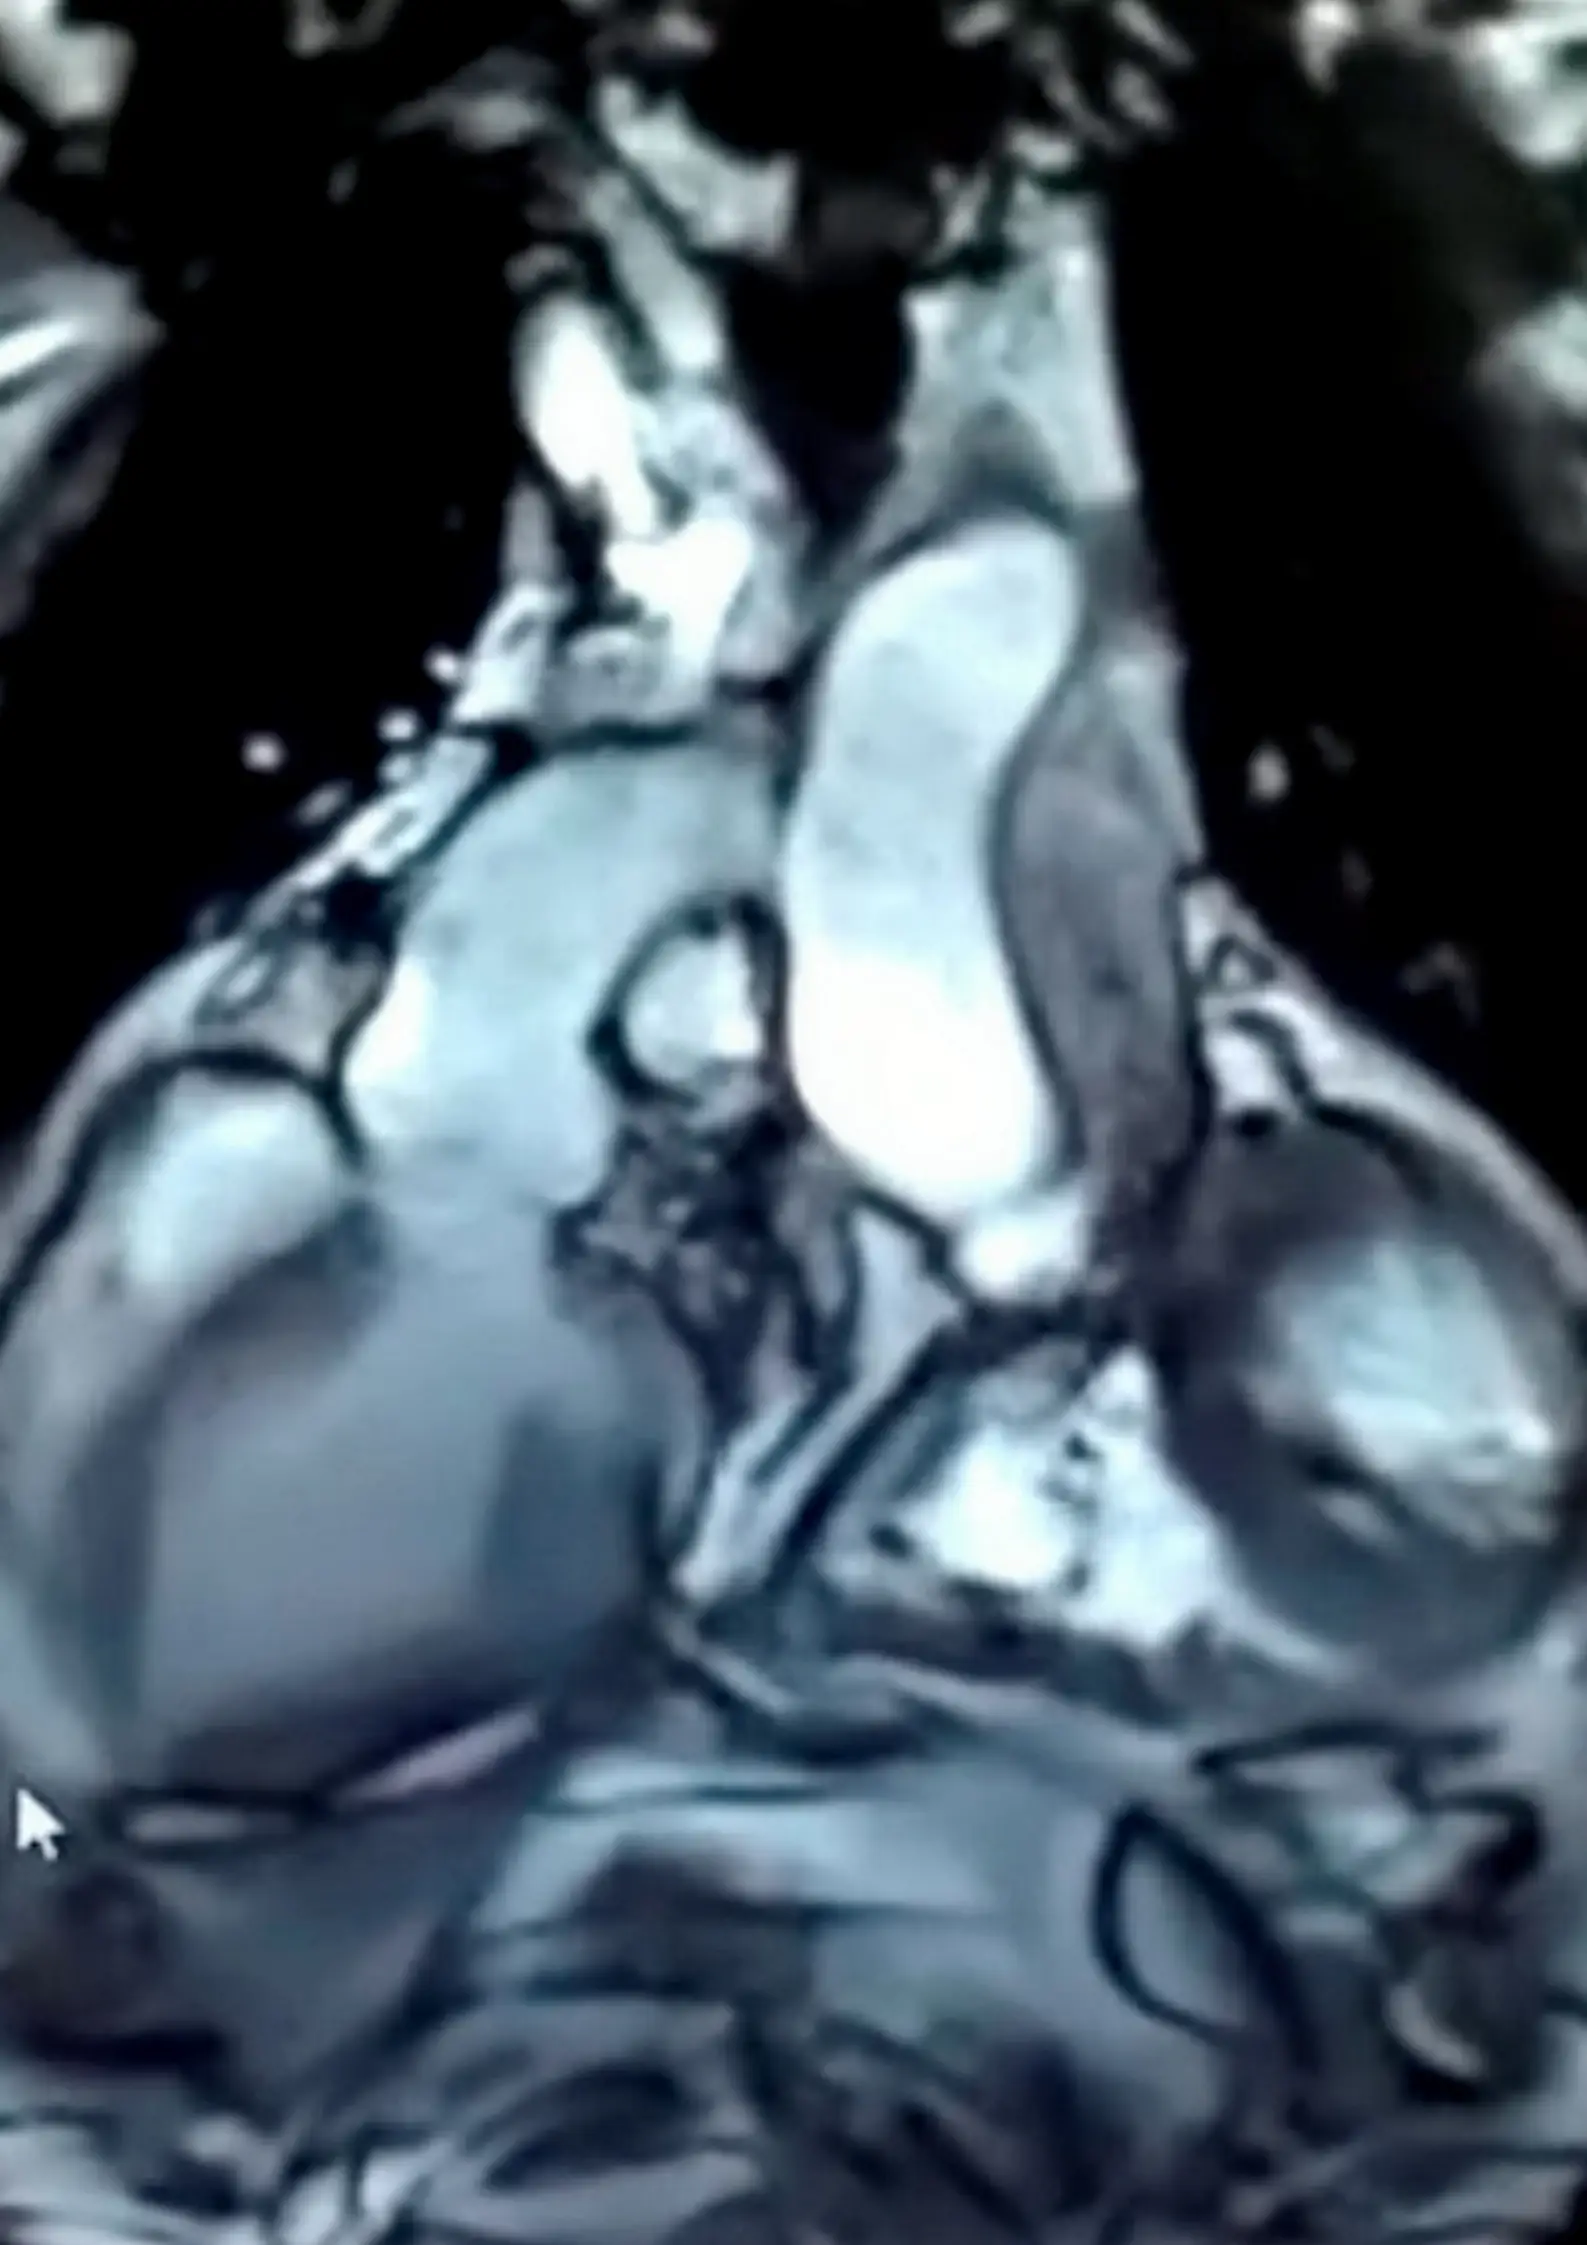

A man who survived a heart transplant now has two hearts beating in his body after medics attached a smaller, female heart to his old one.

Instead, doctors decided to transplant a smaller female heart into his chest cavity - and connected it to his old heart.

Now, Suresh has two hearts beating in tandem in his ribcage, after what is thought to be the first operation of its kind in Asia.

He continued: "There are five connections between the two hearts.

"Two connections are meant to take in the pure blood while three are to take the impure blood while three are to take the impure blood out.

"The two connections placed between the left atriums of the two hearts ensures that blood can be shared.

"Connecting them with the beating heart was the hardest task and that made this operation very challenging."

Suresh's own heart only has ten percent function and sits next to the new one that does the majority of the work.

The healthy donor heart is working in tandem with the diseased one so that the two can successfully carry out the metabolic activities as one, according to Dr Vajyanath.